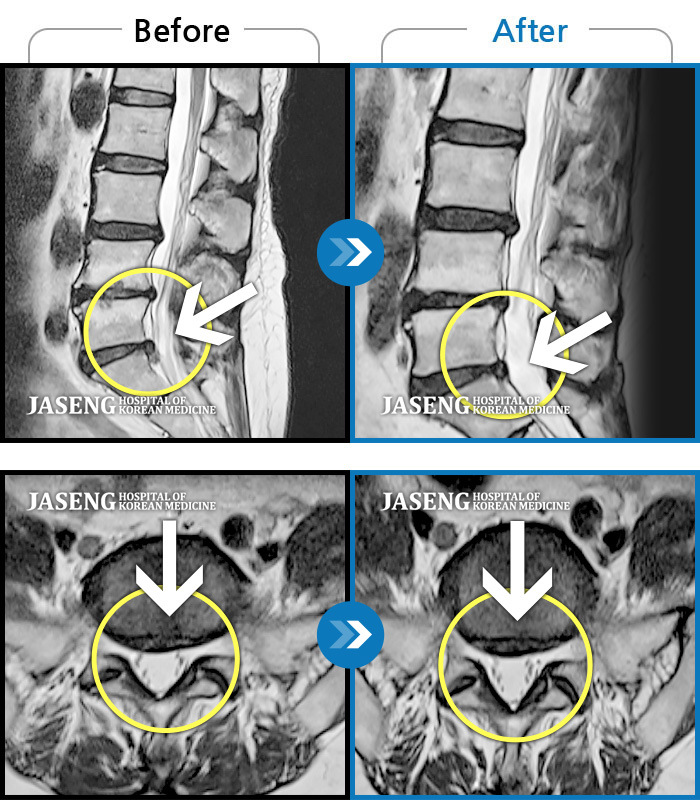

Before

After

환자에게 사전 동의를 받아 동일 조건에서 촬영되었습니다.

개인에 따라 치료 후 부작용이 발생할 수 있으니 의료진과 상담 후 치료를 진행하시기 바랍니다.

허리와 우측골반, 우측다리 통증

"허리디스크 치료하는 동안 예전에 치료 받았던 목디스크도 확인해보고 싶어요”